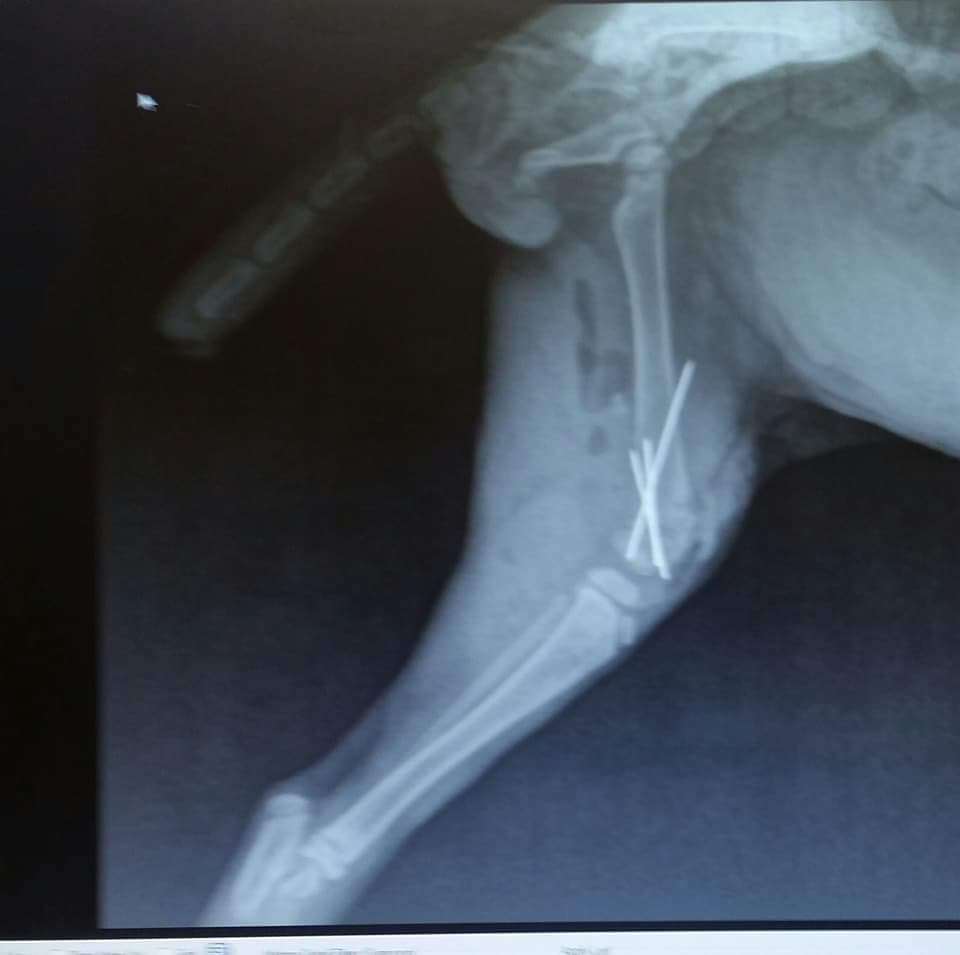

Let me introduce you to the amazing Miracle! This lovely soul has been through the wringer but still shines like the brightest star in the sky! ⭐️ Born on April 4th, 2018, Miracle is a true warrior who's had three major surgeries to save his little body, including a heroic move to become a bobtail. Can you believe that? Talk about resilience and strength! 💪 Imagine being just a kitten and facing such challenges. Miracle was rescued from a most unfortunate situation, having been hit by a car and then found by a kind-hearted good Samaritan named Deb. As if that wasn't enough, he was also left with a severely injured rear leg and a dying tail. 😢 But his luck changed when he was brought to a loving vet who vowed to give Miracle the care he so deserved. This sweet boy has already finished his kitten vaccinations, is FIV and FeLV negative, has been dewormed, is on flea prevention, and he's neutered! Now, although Miracle is officially an adult, he still has that delightful spirit of a playful kitten, and he’s just bursting with joy, love, and sweetness! 🥰 He’s looking for a special home that can appreciate his brave little heart and provide him the love he needs. Plus, a yummy diet of CD canned food is essential for him to thrive! Miracle’s journey hasn’t been easy, but with your support, he can continue to heal and flourish. 💖 Miracle House Animal Rescue is devoted to giving loving animals like Miracle a second chance. Located just east of Cincinnati, Ohio, they work by appointment only once you’re approved to adopt. If your heart is open and you think you can provide a nurturing environment for this precious baby, you can bookmark Miracle in the Buddy App to check back in as he continues to grow and heal. Don’t wait—apply through the Buddy App to make Miracle a part of your family! 🌈